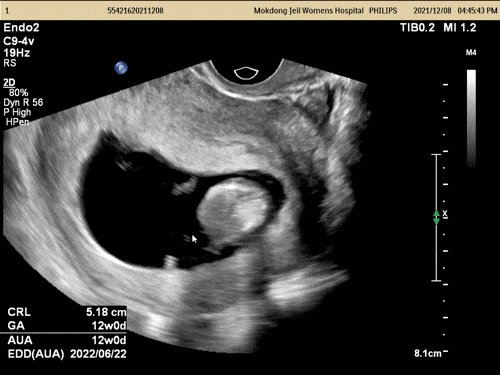

갑자기 3주 사이에 손발이 쑥쑥 자라서ㅜㅜ놀랐다.

12주가 조금 아니었는데 탯줄이 벌써 나와 연결되어 있어ㅜㅜ 신기하다